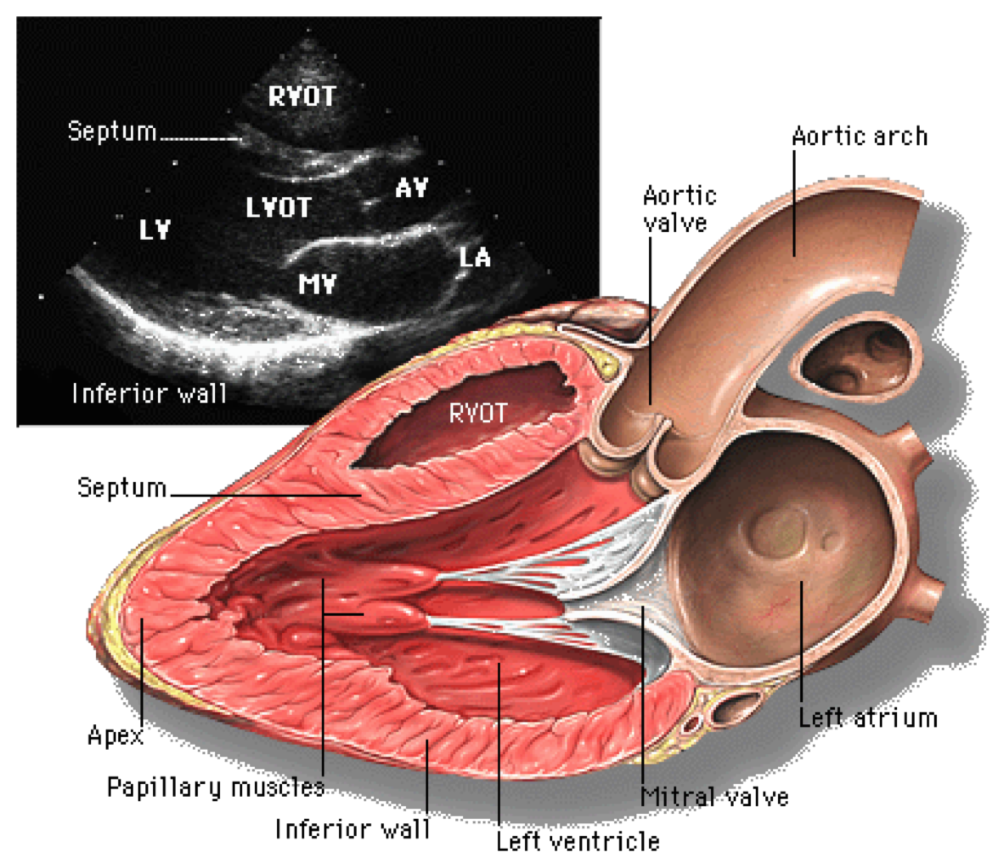

Siêu âm doppler là một kỹ thuật chẩn đoán hình ảnh khảo sát bất cứ dòng chảy nào bên trong cơ thể người dựa vào nguyên lý của hiệu ứng Doppler: Khi một chùm tia siêu âm được phát đi gặp một vật sẽ có hiện tượng phản hồi âm, tần số của chùm siêu âm phản hồi sẽ thay đổi so với tần số của chùm phát đi nếu khoảng cách tương đối giữa nguồn phát và vật thay đổi.

Có 4 kiểu siêu âm Doppler: Siêu âm doppler liên tục, siêu âm Doppler xung, siêu âm Doppler năng lượng, siêu âm Doppler màu. Trong quá trình siêu âm Doppler, đầu dò sẽ được đặt lên da của người được siêu âm và di chuyển trên vùng cơ thể cần kiểm tra. Đầu dò phát ra sóng âm dội lại các vật thể chuyển động. Các sóng âm phản xạ tạo ra hình ảnh chuyển động bên trong cơ thể người. Máy siêu âm sẽ tổng hợp và hiển thị trên màn hình dưới dạng các màu sắc, các dạng sóng phổ khác nhau hoặc tín hiệu âm thanh có thể nghe được.